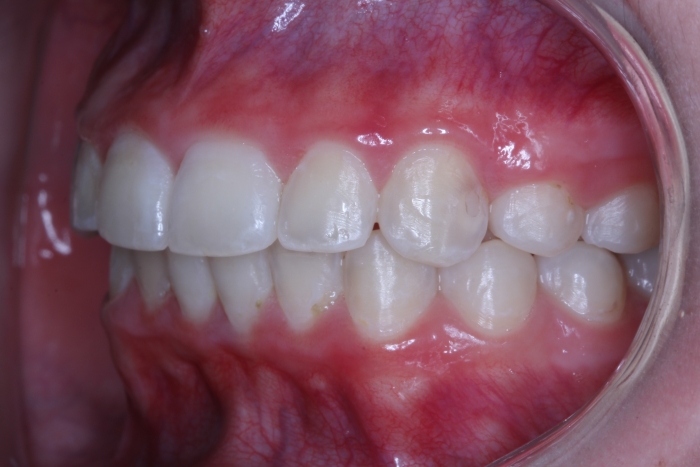

Lateral final - 2019